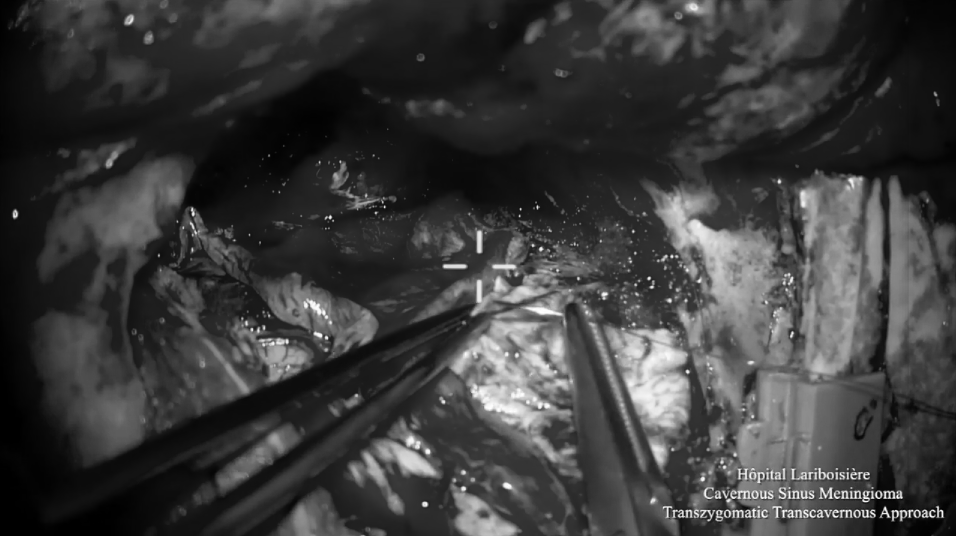

▼使用颧弓入路手术,利用筷子技术神经内镜+显微镜次全切除肿瘤,从海绵窦剥离硬脑膜,切除了浸润的硬脑膜和向颞部延伸的硬膜上脑膜瘤。

▼显微镜下暴露海绵窦外侧壁,注意暴露血管,并进行窦外肿瘤切除。